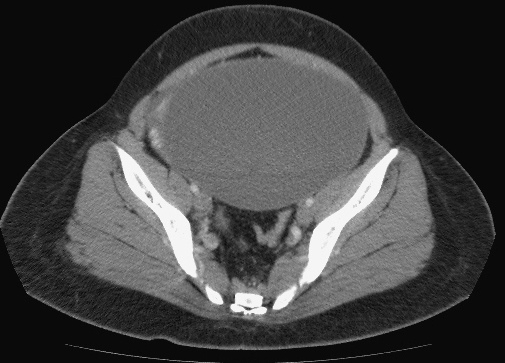

CXR才是診斷的經典:

右側橫膈下方有經典的Free air,

是胃/十二指腸或小腸或大腸破了!一個胃或腸的小破洞,電腦斷層無法判定哪兒破了,一般外科開下去發現是遠端降結腸(Distal descending colon)破了一個洞(0.5 cm),於是找直腸外科繼續完成手術。